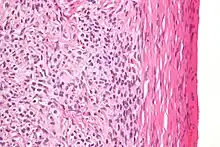

| High magnification micrograph of a thecoma. H&E stain. | |

Microscopically, the tumour cells have abundant lipid-filled cytoplasm.